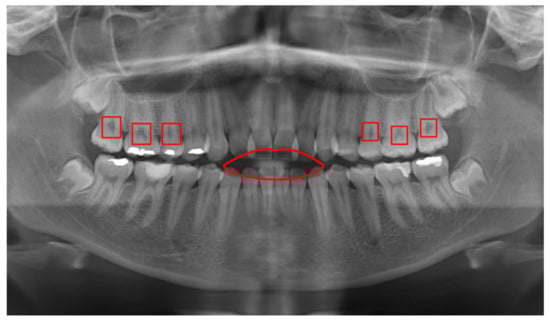

As discussed earlier in Section 1, X-rays have many problems in the quality of acquisition, which caused difficulties in data training, especially the dental panoramic image. The panoramic radiograph contains shadows that are reflections of various structures and organs, such as the lips. It also contains dark spots such as spots in the roots. Those shadows and spots confused the training process and affected the model’s performance. Additionally, the quality of panoramic X-rays is essential for accurately detecting cavities or any lesions. Some panoramic X-rays are poor quality, making it difficult to detect abnormal lesions. Figure 11 presents some examples of shadows and dark areas on panoramic X-rays. Usually, the dentist is familiar with these areas and can determine if this is a lesion or a fake spot. In contract, the deep learning models may fail to identify these issues.

Figure 11. An example image from the Ivisionlab dataset that illustrates the drawbacks of panoramic images in which the red color indicates the shadows of the tongue and gingival pocket.